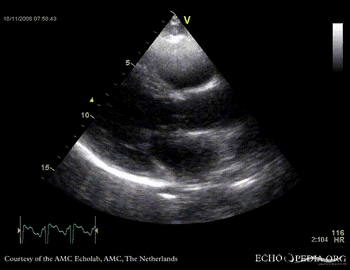

Rupture of the ventricular septum

VSR 8